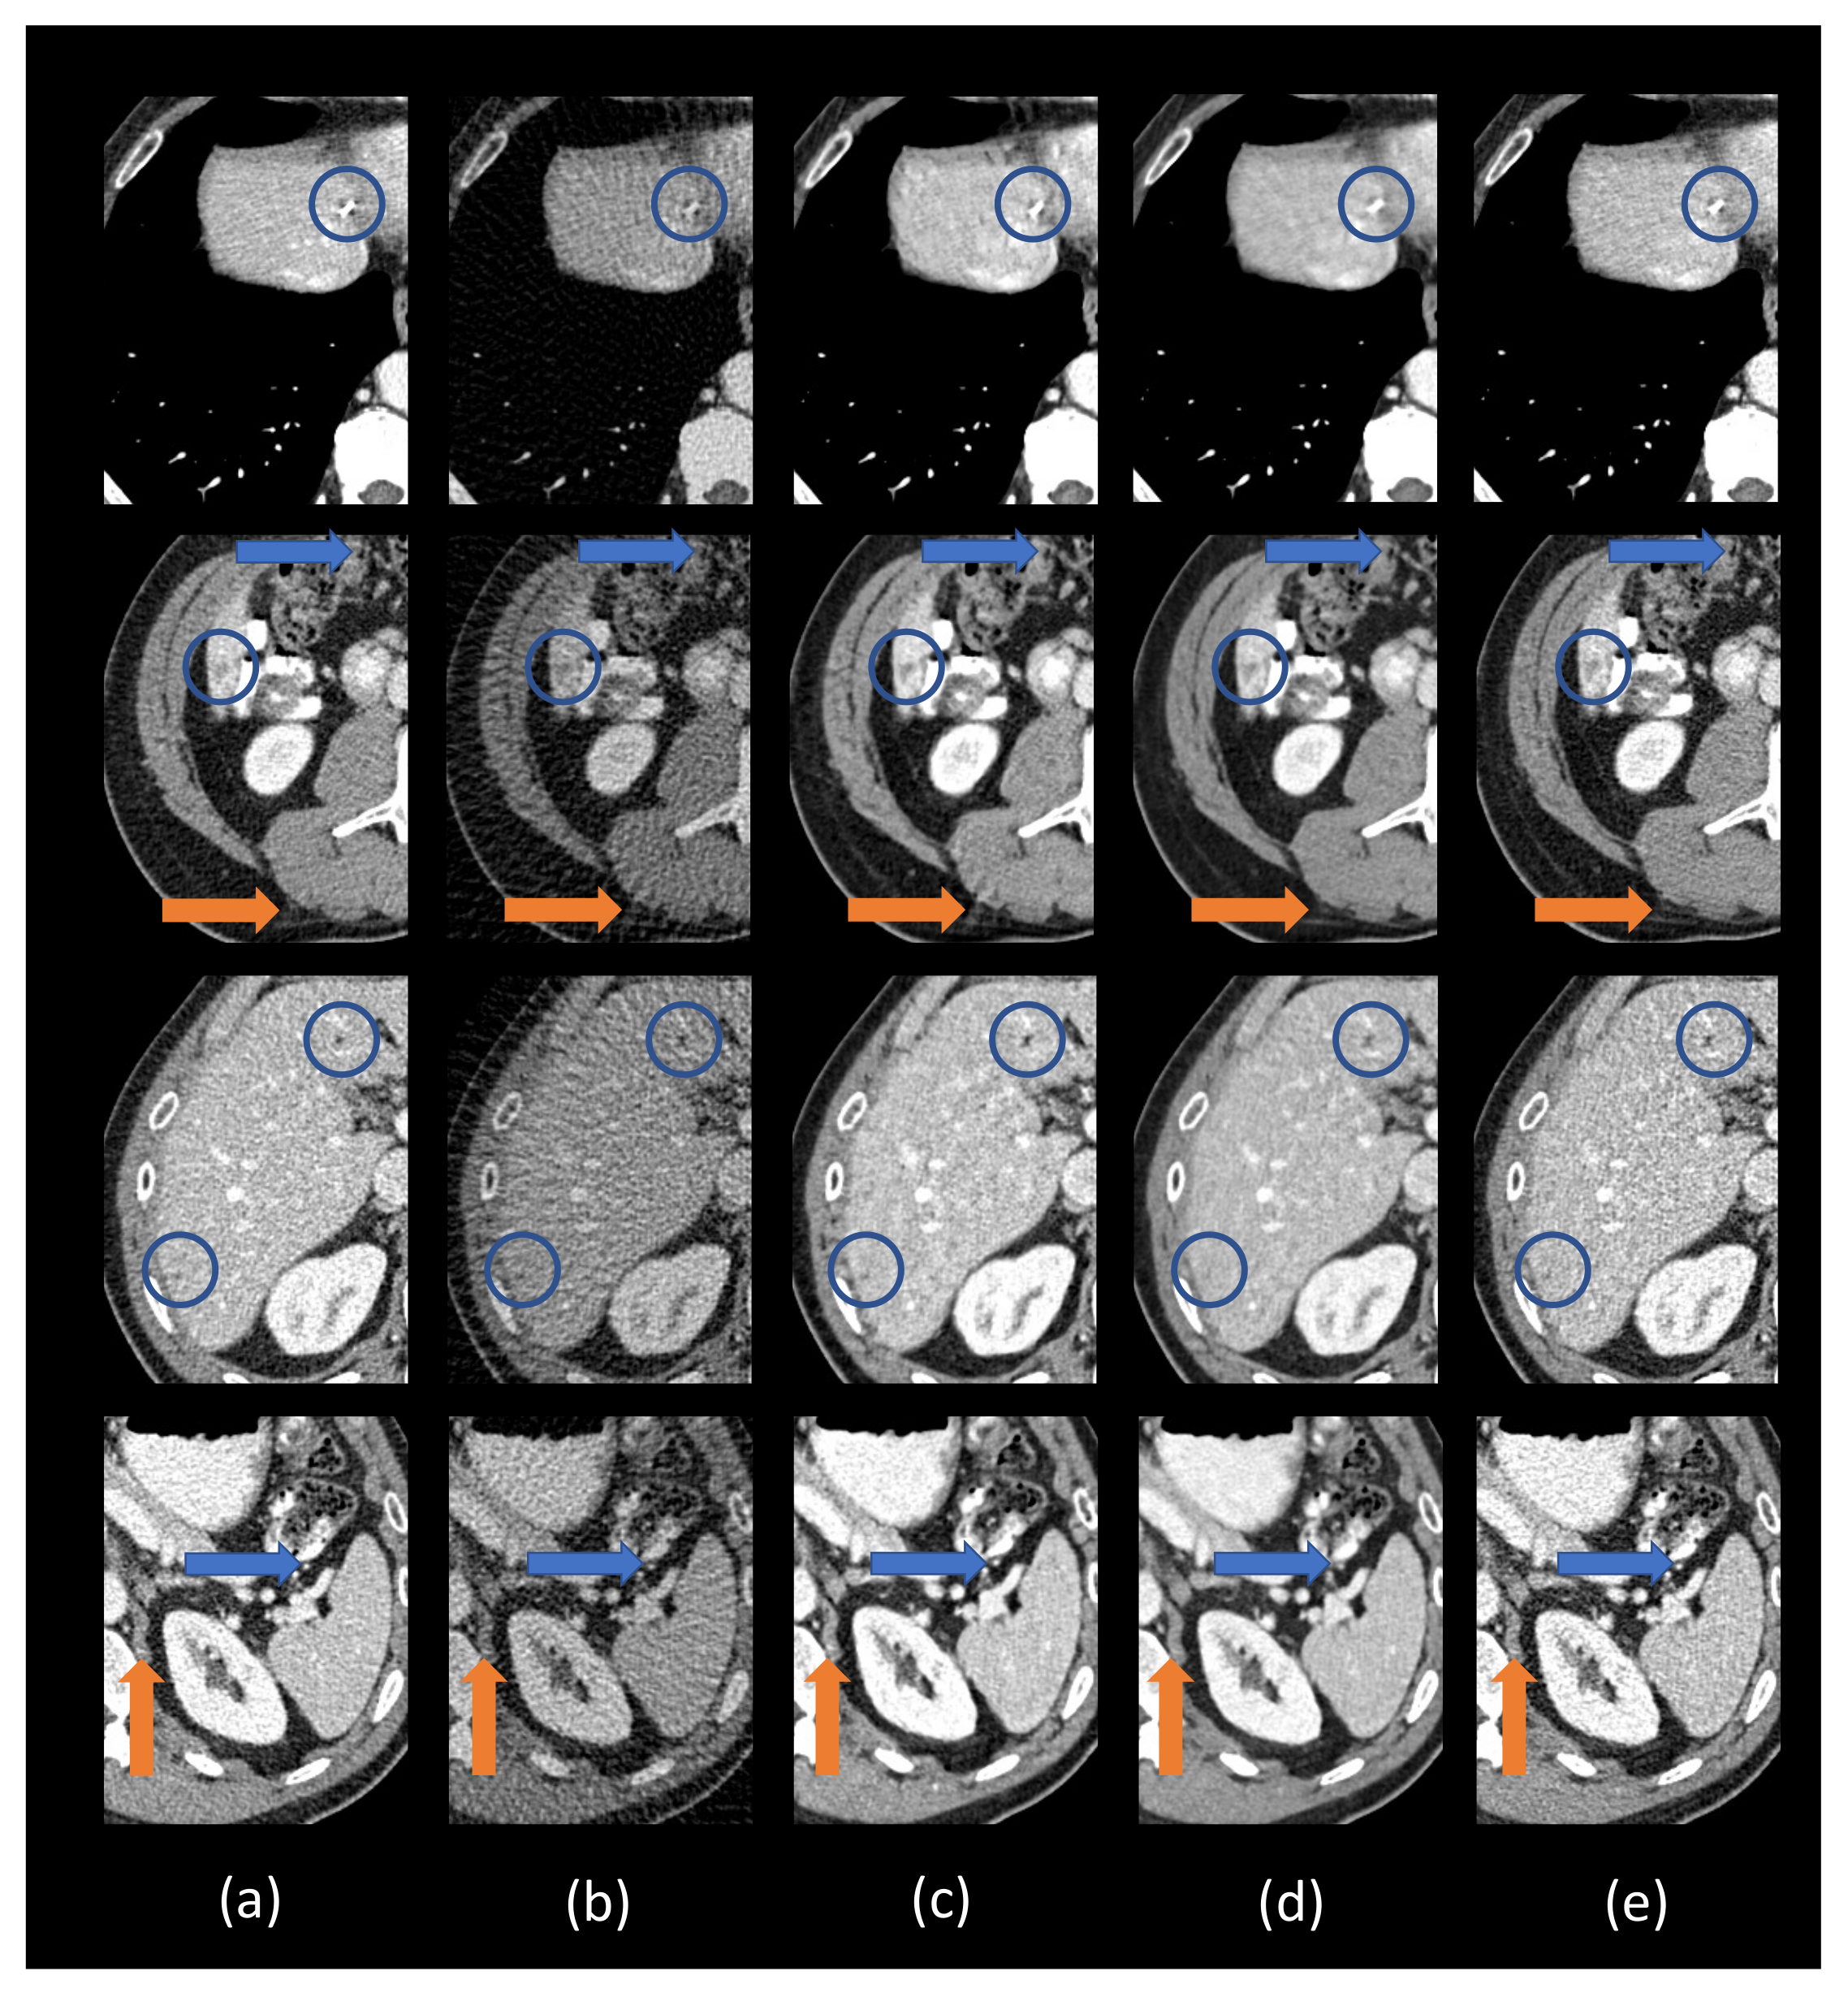

3.2. Hyperparameter Selection and Network Comparison

3.3. Comparison with Other Deep Learning Methods

3.4. Ablation Analysis